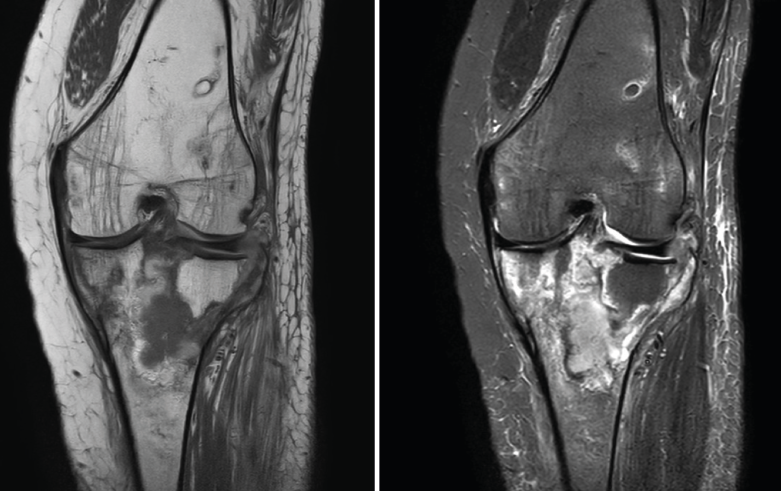

4.3. Osteocondritis

En la osteocondritis se aprecia una lesión subcondral caracterizada por resorción ósea, colapso y la formación de un secuestro.

El estudio por RM es una herramienta valiosa para diagnosticar e identificar las lesiones del cartílago. Conocer el aspecto del cartílago y saber cuánto y cuándo se lesiona, basándose en las clasificaciones actuales, permiten al radiólogo proporcionar la máxima información al clínico(20).

Numerosos estudios demuestran la utilidad de la RM para definir la estabilidad o inestabilidad de la lesión en la osteocondritis, destacando su carácter no invasivo y la capacidad de valorar la progresión y la respuesta al tratamiento(21) (Figuras 53 y 54).

Figura 53. Corte de secuencia sagital (A) y axial (B) T2 Fat-Sat de RM de rodilla: lesiones osteocondrales en el fémur y la rótula.

Figura 54. Corte de secuencia T1 y T2 Fat-Sat coronal de resonancia magnética: gran osteocondritis en el cóndilo femoral interno con edema en la medular adyacente.